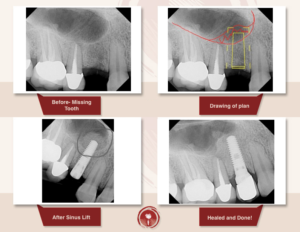

Синус ліфтинг

Операція синус ліфтинг

Це хірургічна операція по нарощуванню кісткової тканини в бічних відділах верхньої щелепи, для якісного встановлення імплантатів.

Як одна з методик автокісткової пластики, синус ліфтинг щелепи дозволяє відновити необхідний обсяг кісткової тканини альвеолярного відростка в передбачуваній області фіксації імплантату, за рахунок зменшення простору верхньощелепної (гайморової) пазухи.

При більшій пневматизації показаний закритий синус ліфтинг або м’який (soft) з доступом через канал ложа імплантату.

При наявному обсязі кісткової тканини менше 5 мм показаний відкритий синус ліфтинг – пластика дна верхньощелепної пазухи з доступом-перфорацією передньої стінки пазухи.

Традиційно вважається, що повний цикл репаративного остеогенеза (регенерація кісткової тканини) становить півроку, але виробники остеоіндуктівних матеріалів повідомляють про формування необхідної механічної міцності тканин через 4 місяці.

Таким чином, на цьому терміні доречно проведення рентгенологічного обстеження з метою визначення обсягу сформованих тканин, їх рентгенологічної контрастності і щільності, тобто ступенем мінералізації і придатності до установки імплантатів.